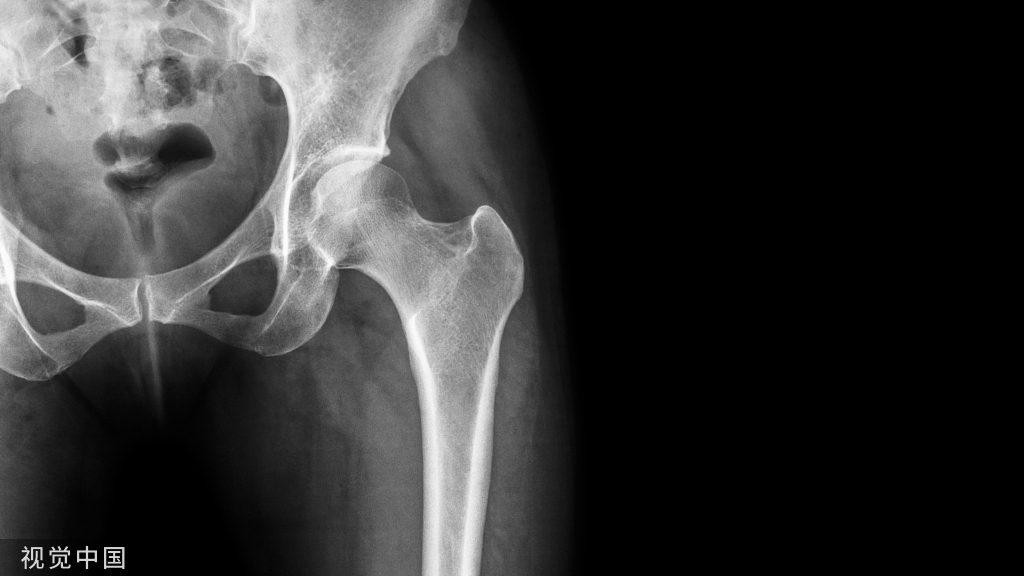

Kummell病是指在无明确的暴力外伤下的情况下,逐渐出现进行性腰背疼痛和后凸畸形的疾病,患者以老年人多见,常伴骨质疏松。

Kummell病是指在无明确的暴力外伤下的情况下,逐渐出现进行性腰背疼痛和后凸畸形的疾病,患者以老年人多见,常伴骨质疏松。影像学提示椎体塌陷或者出现椎体裂隙征,排除新鲜骨折、肿瘤、感染等明确病因后,都可以认为是Kummell病。